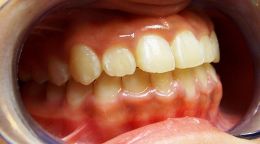

Soggetto asiatico con morso inverso anteriore completo.

Crescita scheletrica tendente alla terza. Impossibilita di determinare il carico genetico del problema.

finalmente la paziente comincia il trattamento intercettivocon il damon 4 x 2

inserimento e funzionalizzazione di 4x 2

le molle open coil agiscono sviluppando il mascellare superiore e correggendo il rapporto di classe dentale ,lentamente e dolcemente ,le forze leggere continue possono correggere il problema iniziale che altrimenti avrebbe preso il sopravento nella crescita della bimba .

corretto il crossbite si partecipa alla corezione dentale lentamente e dolcemente.